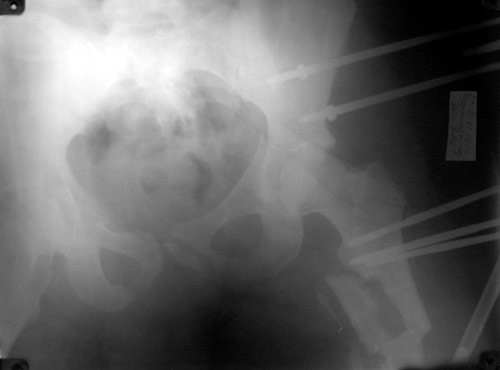

Таз

Бедро

То, что получилось в приложении. Стоит ли дальше тянуть головку винтами или низводить проксимальный отломок по оси?

С> То, что получилось в приложении.

Можно только порадоваться за пациента и врачей, положение отломков значительно улучшилось. Может быть, удастся добиться "вторичной конгруэнтности" даже при сохраняющемся диастазе на уровне перелома. Из того, что видно - стержней в тазу маловато, лучше бы зацепиться за гребни подвздошных костей (по 3-4 стержня), тогда можно будет пациента и поднять на костыли.

С> Стоит ли дальше тянуть головку винтами или низводить проксимальный

С> отломок по оси?

Возможно, и то, и другое. По одной прямой проекции ситуацию не оценить - желательно сделать косые проекции (Judet) левой вертлужной впадины, на которых будет видно, конгруэнтна ли головка со сводом, не надо ли подвинуть ее кпереди или кзади.

По бедру - ось (по одной проекции) и длина восстановлены. Непривычно выглядит стержень с медиальной стороны, мы обычно обходимся только

наружной полуокружностью бедра. Если аппарат здесь предполагается как окончательный фиксатор - похоже, это надолго...

На первый взгляд репозиция вертлужной впадины не плохая, однако следует сделать проекционные снимки по Judet, а вот аппрат конечно подкачал, да и больного жалко. Былобы красиво сейчас после рентген-контроля перкутанно ппровести стягивающие винты через перелом вертлужной впадины из подвздошной в лобковую и из седалищной в подвздошную. А бедро заштифтовать, а потом снять аппарат и отпустить больного, передний отдел возможно фиксировать АВФ.